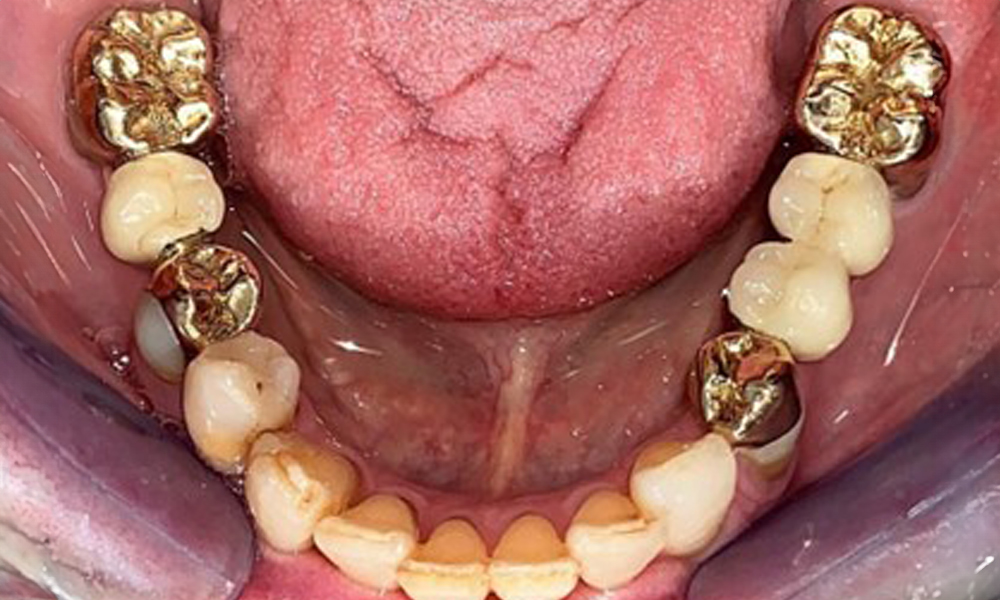

Occlusal view of the mandible.

Fig. 4: Occlusal view of the mandible.

The patient was fitted with a combined removable maxillary telescopic prosthesis more than 25 years ago (Fig. 1, Fig. 2, Fig. 3) and is very happy with her dentures. The patient has an adequate fixed denture for the mandible (Fig. 4).

The dental findings are as follows: Combined removable implant and tooth-supported telescopic prostheses on implants 15, 13, 21, 23, 24, 25 and tooth 11 (Fig. 1, Fig. 2, Fig. 3). The patient was fitted with a fixed mandibular denture. Adequate bridges were present over 37 to 34 and 45 to 47 (Fig. 4), the crown margins were intact and there were no active caries. A composite filling with a marginal gap was present on tooth 43. There was mandibular gingival recession, exposing 1 to 3 mm of root surface. This also applies to 11.